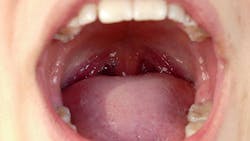

The tonsils offer many nooks and crannies that bacteria can use to thrive. The multiplying bacteria can become trapped, allowing mucous and dead cells to linger and form tonsil stones in the pockets of the tonsils.1 Tonsil stones, also known as tonsilloliths, are formed when the trapped debris calcifies. The stones can lead to chronic inflammation and discomfort.

The most common symptom (and often the only symptom patients experience) is halitosis. If the tonsil stones are left untreated, bacteria continue to multiply and increase the inflammation of the tonsillar tissue. Symptoms of a severe throat and discomfort when swallowing are frequently experienced with tonsil stones that have gone undiagnosed and untreated. Additionally, patients can experience ear pain due to the swelling of the tonsils.1

Properly screening the patient for abnormalities through a head and neck exam will allow the clinician to identify the presence of tonsillar inflammation and stones. If left untreated, tonsil stones can lead to severe throat and ear pain. Chronic tonsil stones can lead to the removal of the tonsils, which are a vital part of the immune system.